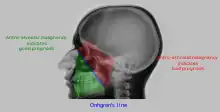

A Waters' view radiograph showing the paranasal sinuses

Onhgren's line

• Distance between antero-lateral wall of maxilla and coronoid process of the mandible is measured. If it is increased on one side, it indicates involvement of infratemporal fossa by the malignancy. This is called Handousa's sign. Prognosis of malignancy is determined by position of tumour on basis Onhgren's line.